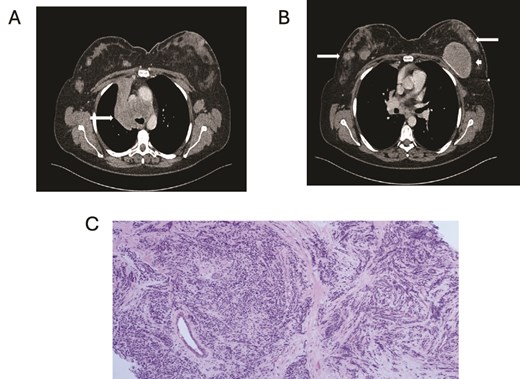

A 46-year-old female with a 20-year history of left breast augmentation performed for asymmetry, and a significant smoking history (55 pack-years), presented with a well-defined palpable lump in the upper outer quadrant of her right breast. On clinical examination she had bilateral breast lumps, initially suspected to be benign. Mammography and ultrasound imaging confirmed multiple bilateral breast masses, as well as an intracapsular rupture of the left breast implant (Fig. 1). The masses were classified as M2 (benign) on mammogram and U3 (indeterminate) on ultrasound, with an enlarged left axillary lymph node also identified. Core needle biopsies from the left breast mass and left axillary lymph node revealed metastatic involvement from a primary small cell carcinoma of the lung. Further staging with CT imaging revealed a contralateral right-sided lung tumor, along with extensive metastases to the hilar and mediastinal lymph nodes, liver, and pancreas (Fig. 2).

(A) Axial contrast enhanced CT shows right hilar mass. (B) CT scan showing bilateral breast metastasis (arrow) and left breast implant (arrowhead). (C) Cores of breast tissue infiltrated by malignant cells with high nuclear: cytoplasmic ratio, inconspicuous nucleoli and nuclear molding. The appearances are of small cell carcinoma.